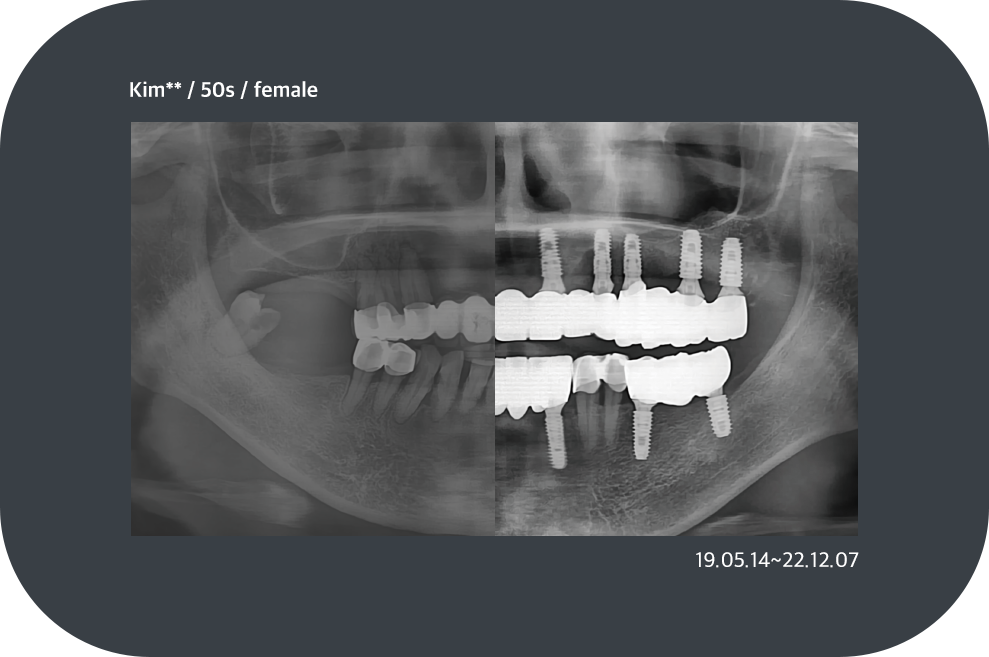

치료사례

임플란트 치료사례

implant_case01

implant_case02

implant_case03

implant_case04

*모든 증례 사진은 의료법 제23조, 제56조에 의거하여, 당사자의 동의하에 게시하였습니다.

*치료 사진은 모두 본원에서 치료한 환자분의 사진입니다.

*치료 사진은 모두 동일인의 사진이며, 동일조건에서 촬영하였습니다.

*개인의 차이에 따라 시술 및 수술 후 부작용이 발생할 수 있으며, 의료진과 충분한 상담을 받으시기 바랍니다.